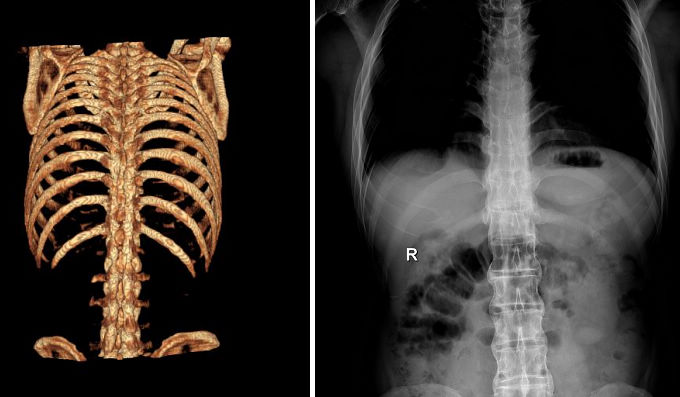

QZ16030094 姓名:陈先生 性别:男 年龄:32岁

- 病情

AS ①晚期 ②重度 病史:5年+

- 治疗

治疗后骶髂关节疼痛消失,腰椎前屈、背伸侧弯活动自如,膝关节无压痛感,复查血沉、C反应蛋白、等各项检查均已达到临床康复的标准。